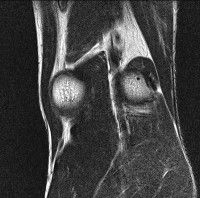

무릎 mri 간단히 봐주실 수 있으시나요 ㅠㅠ

안녕하세요 8년전 십자인대 수술하고 최근 무리한 운동에 무릎 불편감이 생겨서

mri 찍었습니다.

진단결과는 첫 찍은 병원에서 활액막염 이라는 진단을 받았습니다. 혹시 봐주실 수 있으실까요?

올라온 MRI가 단편적이라서 정확한 진단에 어려움이 있지만 십자인대에는 큰 이상이 있지는 않은것 같으며, 무릎관절내 물이 있는 것으로 보아 활액막염의 진단이 맞을 것 같습니다.

하지만 단편적인 영상이기 때문에 촬영병원에서 정확한 판독지 등을 받으시는 것이 좋겠습니다.